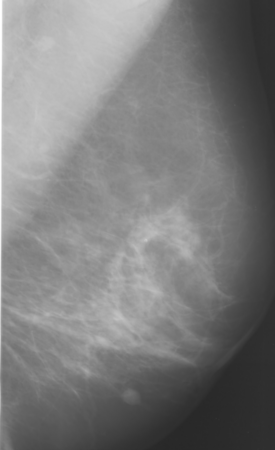

A typical example of image registration applied to mammographic

images is shown below.

| Reference Image |

Image to be Warped |

Difference After Registration |